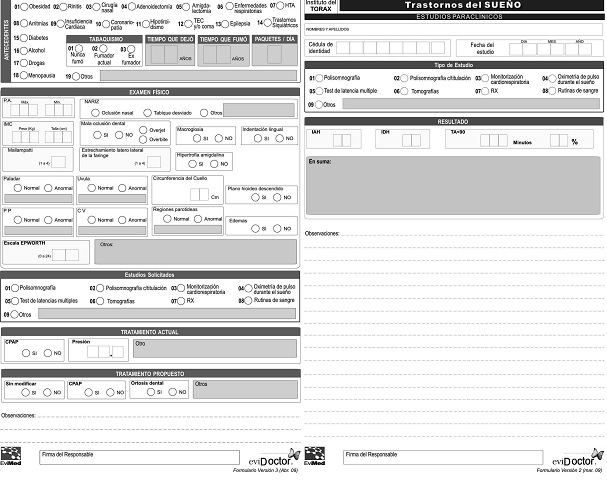

La frecuencia con que fueron referidos los pacientes mostró un aumento persistente en el período 1991 a 2014. La realización de polisomnografías, pasó de 20 a 346 por año, sin diferencias entre el crecimiento en Hospital de Clínicas y el sistema mutual (Figura 1).

Figura 1: Número de pacientes referidos por año. Barra de color oscuro: número de pacientes referidos al Hospital de Clínicas. Barra de color claro: número de pacientes referidos al sistema mutual.

Se apreció una frecuencia mayor de los pacientes del sexo masculino en la práctica mutual (71,9%), con respecto al Hospital de Clínicas (42.8%). La media de edad en el momento de la consulta fue de 52,7 ± 13,5 (rango 5 a 92), con un máximo en la década de 51 a 60 años, y una distribución homogénea en las otras décadas.